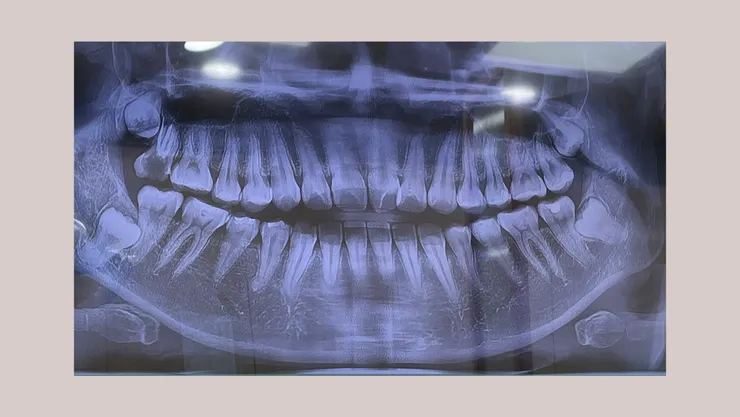

X光照🩻

X 光正面照,明顯看見我的上排門牙開開的